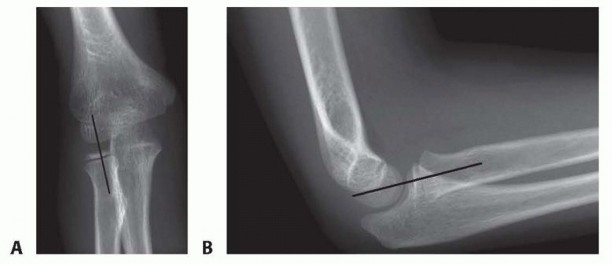

FIG 7 • In a normal elbow, the radiocapitellar line generally bisects the capitellum. A disruption of the radiocapitellar line is concerning for radial head subluxation or dislocation but due to variation in the normal pediatric population is not pathognomonic for a Monteggia lesion. A. AP elbow radiograph in a 7-year-old girl demonstrating a normal radiocapitellar line. B. Lateral elbow radiograph in a 7-year-old girl demonstrating a normal radiocapitellar line.